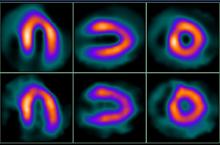

Cardiac hybrid imaging combines coronary computed tomography angiography (CCTA) and myocardial perfusion imaging with single photon emission tomography (SPECT) to provide information on both stenosis and perfusion. The approach has shown promise in studies focusing on short-term observations, but information is lacking on long-term outcomes.

The research team looked at 428 patients who underwent hybrid imaging. During a median follow-up of 6.8 years, a total of 160 major adverse cardiac events, including 45 deaths, were observed in the final study population. Patients with matched findings — stenosis of 50 percent or more on CCTA with evidence of ischemia on SPECT in the area of the heart to which the blocked vessel was supplying blood — had more than five times the risk of adverse events than those with normal findings. Patients with unmatched findings, or evidence of ischemia but not in the area of the heart being fed by the stenotic artery, had three times the risk. Major adverse cardiac event rates were 21.8 percent for matched findings and 9 percent for unmatched — considerably higher than the 2.4 percent rate for normal findings.

The study supports CCTA use for an initial, noninvasive evaluation of patients with known or suspected stable coronary artery disease. No additional imaging would be necessary if the results were normal. If a lesion was evident, then clinicians could employ a nuclear scan to assess ischemia and take advantage of both modalities by fusing the results together to make a hybrid image.

The researchers hope to run a trial to show that hybrid imaging can have a positive impact on patient outcomes. They are also looking at what they call “triple hybrid” imaging, which combines the CCTA/SPECT hybrid with information on coronary artery shear stress. The shear stress information could help identify lesions that do not yet have an impact on ischemia but will in the future.